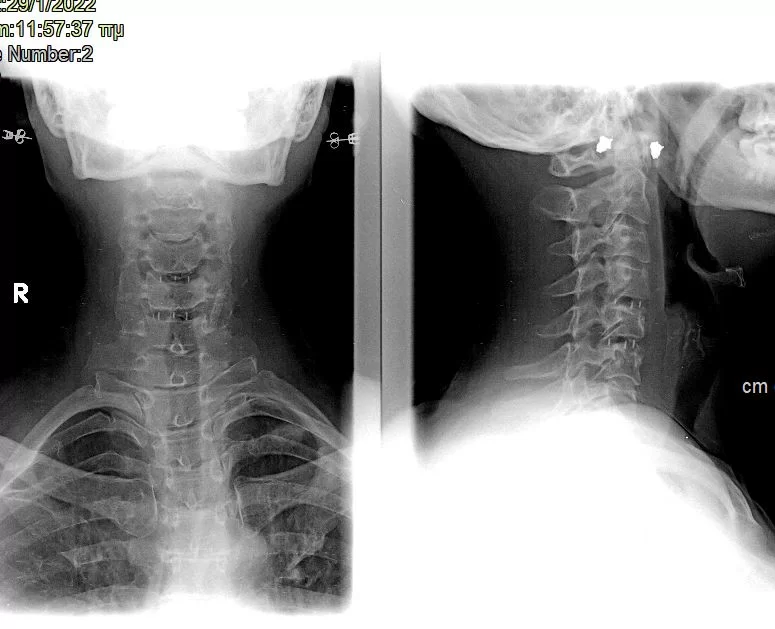

Ψευδάρθρωση μετά από σωματεκτομή Α5 & Α6 – Σπονδυλοδεσία ΑΜΣΣ 360ο

Ασθενής γυναίκα 43 ετών με ιδιαίτερα έντονο άλγος αυχένα και δεξιού άνω άκρου (κατανομής κυρίως Α7 ρίζας). Συνοδός ζάλη, τάση προς έμετο και δυσφαγία. Ο